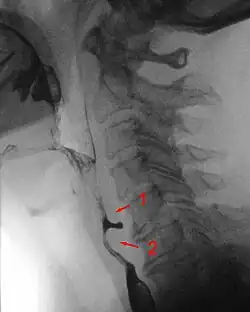

Radiologen teilen die Zenker-Divertikel nach Brombart in vier Stadien zunehmender Schwere ein:

- Stadium 1 ist eine dornenförmige, 2–3 mm lange Nischenbildung, die auch nicht immer sichtbar wird.

- Divertikel im Stadium 2 sind 7–8 mm groß und keulenförmig.

- Divertikel im Stadium 3 sind über 10 mm groß, sackförmig und nach unten umgebogen.

- Im Stadium 4 komprimiert das Divertikel die Speiseröhre und behindert sichtbar dessen Kontrastmittelpassage.[3]

Die Diagnostik erfolgt bei entsprechenden Symptomen mit der Endoskopie und Röntgenaufnahmen mit Kontrastmittel. Sobald ein Patient Schluckstörungen bemerkt, sollte er sich in fachärztliche Betreuung begeben, denn diverse Erkrankungen der Speiseröhre können diese Beschwerden hervorrufen. Danach sollte eine genaue Inspektion von Mund und Rachen des Patienten erfolgen und der Hals nach vergrößerten Lymphknoten oder Weichteilveränderungen abgetastet werden. Je nach Verdachtsdiagnose wird eine Spiegelung der Speiseröhre durchgeführt und gleichzeitig im Bereich auffälliger Schleimhautbereiche eine Gewebeprobe entnommen. Ergänzend, vor allem bei Divertikeln, wird eine Röntgenuntersuchung der Speiseröhre mit flüssigem Kontrastmittel durchgeführt, die auch Bewegungsstörungen der Speiseröhrenwand zeigen kann. Handelt es sich bei der Erkrankung um einen Tumor, ist es unter Umständen notwendig, eine zusätzliche CT- oder MRI-Untersuchung durchzuführen, um seine Ausdehnung und Lage im Brustkorb zu sehen. Unter Umständen ist auch eine Voruntersuchung durch einen Hals-Nasen-Ohren-Arzt notwendig, der die Funktionsfähigkeit eines wichtigen Nervs im Bereich des Kehlkopfes überprüfen muss. Je nach Vorerkrankungen und Alter des Patienten werden auch Ultraschalluntersuchungen am Herzen sowie eine Lungenfunktionsprüfung durchgeführt. Bei einem Zenker-Divertikel ist die Indikation zur Operation gegeben, völlig unabhängig davon, wie stark die Beschwerden des Patienten sind, denn die Komplikationsrate ist gering.